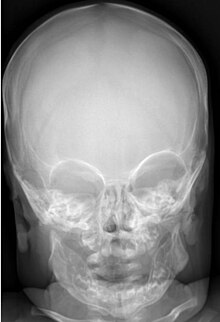

Macrocephaly (right) vs. normocephaly (left)